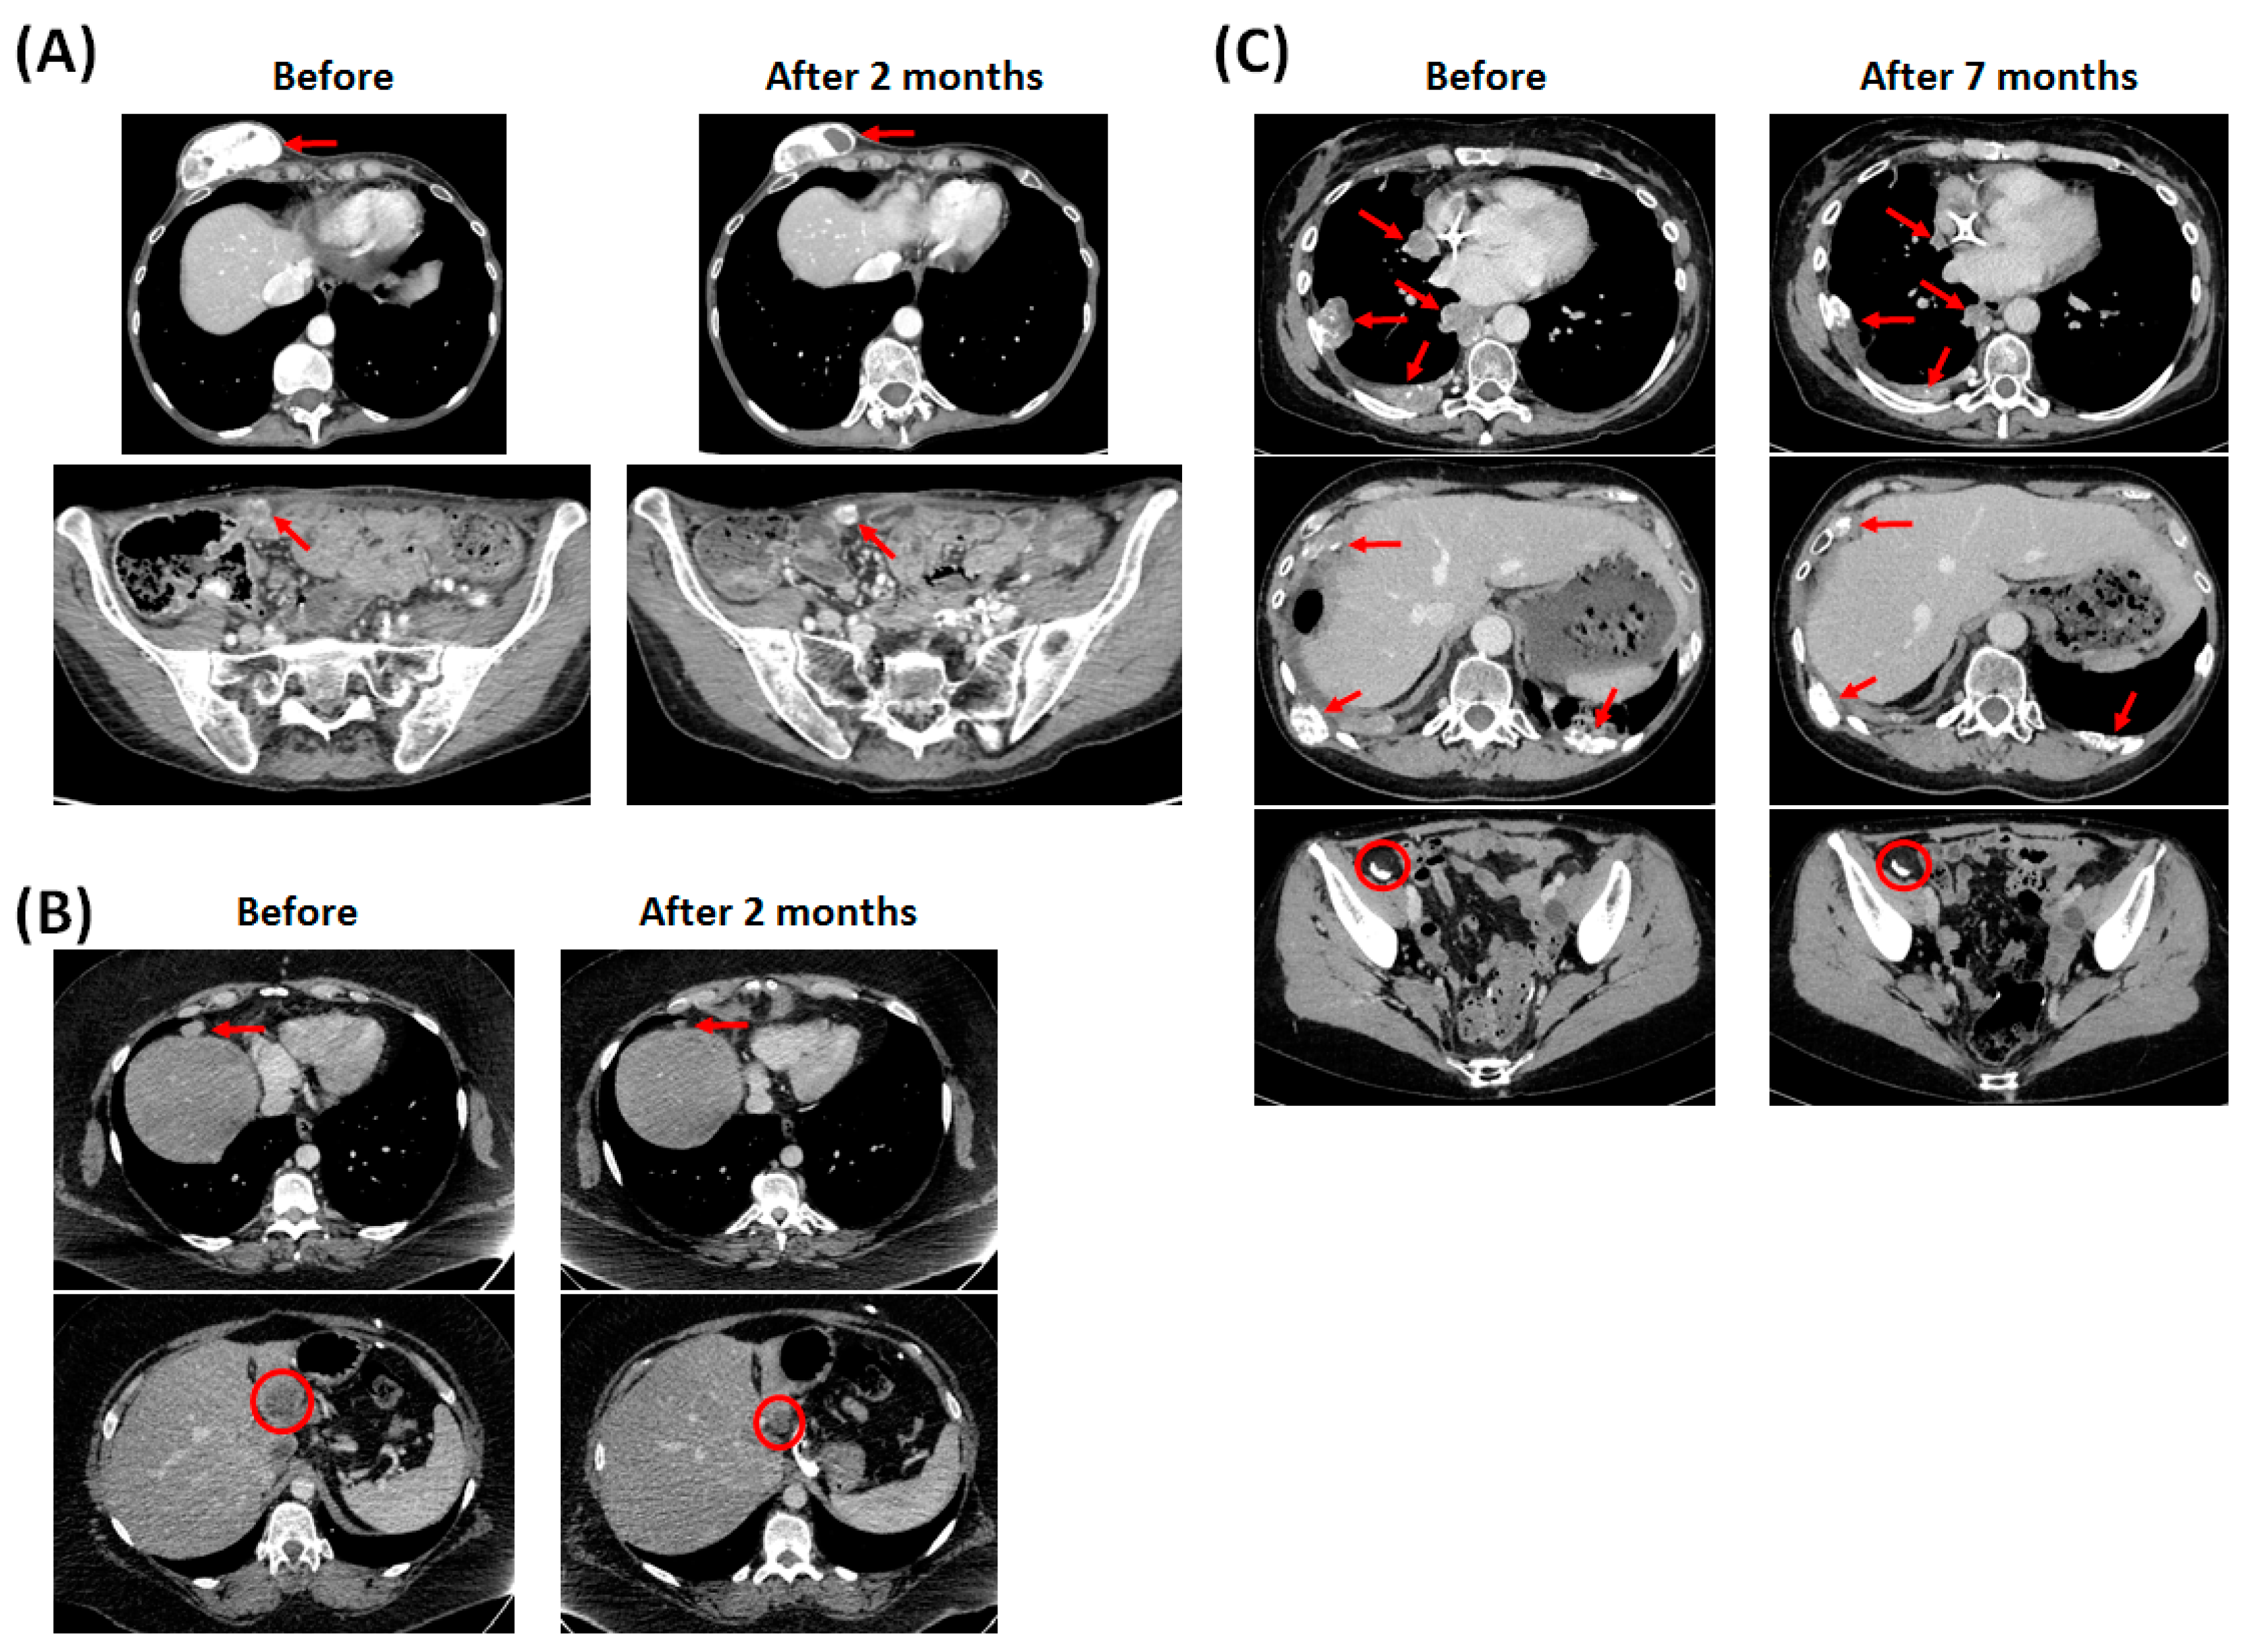

2.2.2. Clinical Observations